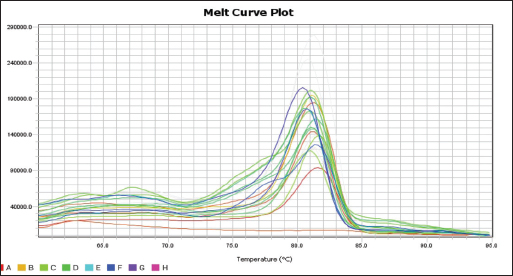

Fig. 2. Blood smear indicates Mycoplasma haemofelis invades equine RBCs. Fluorescent microscopy,0.1% acridine orange staining. 1000X. qPCR resultIn the current study, 79%(79/100) of diseased horses were found to be positive using qPCR (Figs. 3 and 4). The agreement between the two diagnostic methods was analyzed using Cohen's Kappa statistic. The observed agreement was 91% (91/100), and the expected agreement by chance was 72.04%. The calculated Kappa coefficient was κ=0.678 (95% CI), indicating substantial agreement between cytological and qPCR diagnoses according to the Landis and Koch benchmark Table 1.

Fig. 4. Melt curve plot of the 16S rRNA gene of mycoplasma haemofelis positive samples. Table 1. Diagnostic agreement analysis between cytological examination and qPCR for the detection of equine Hemomycoplasmosis